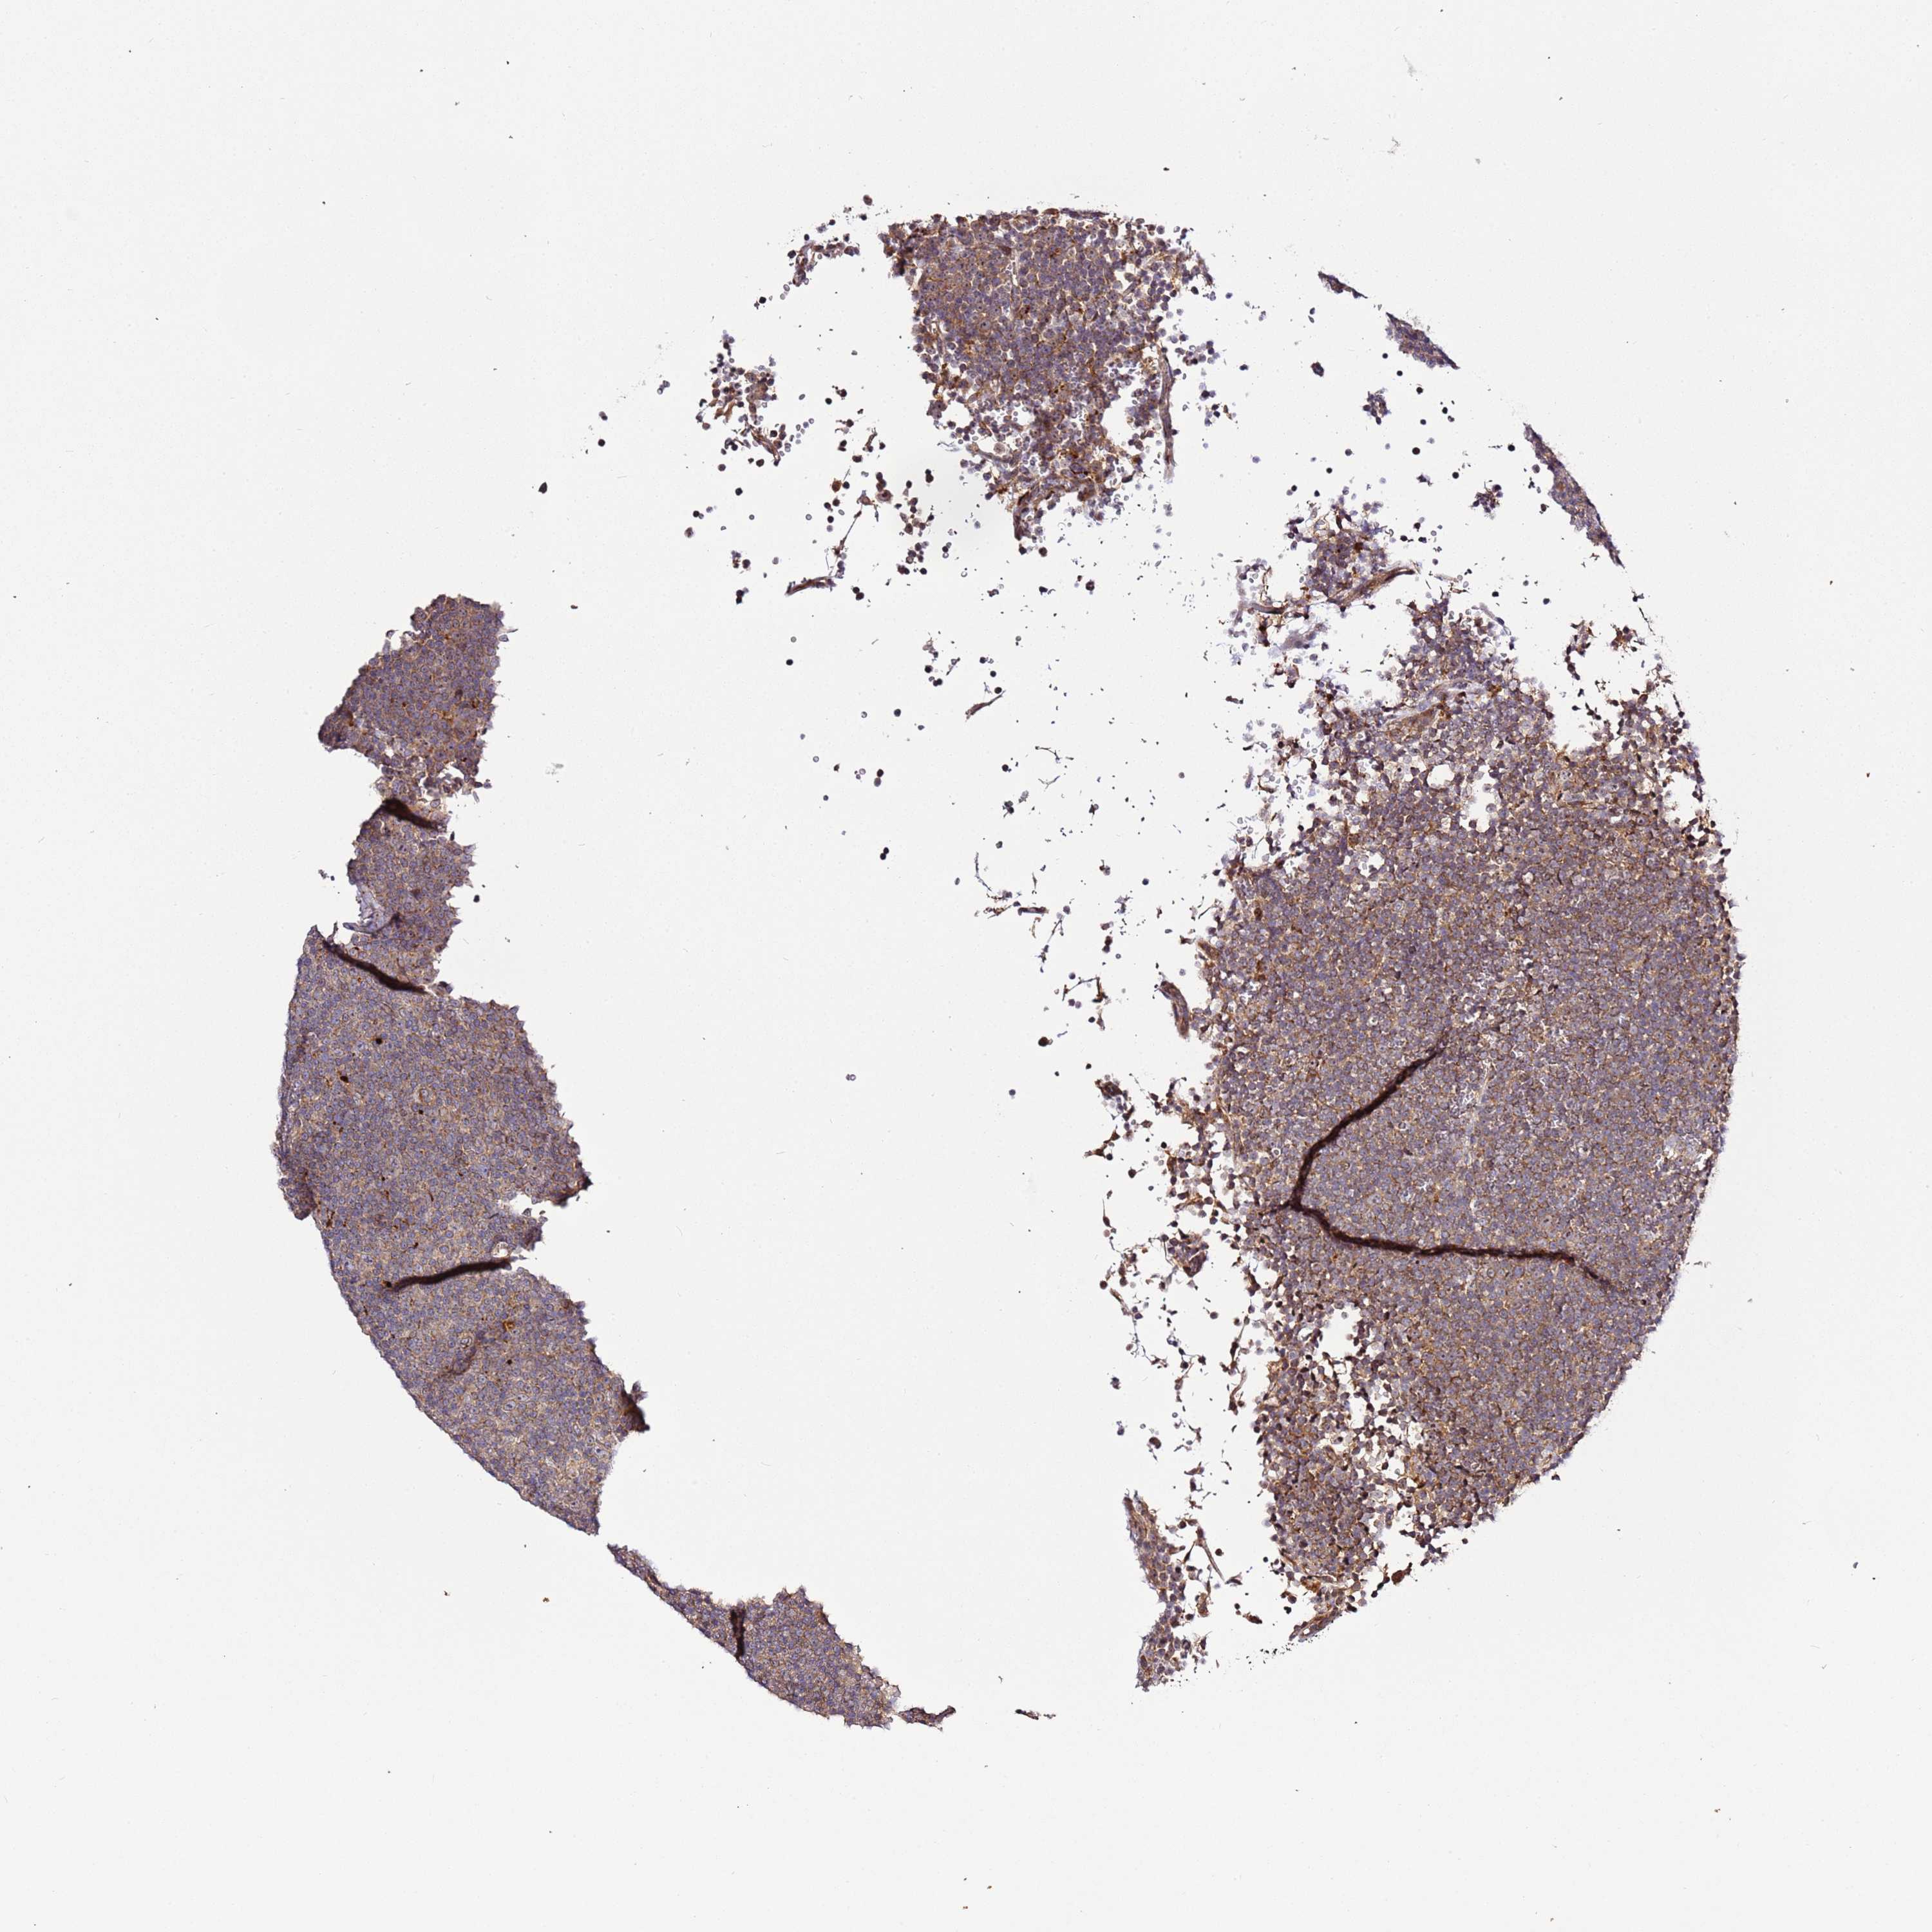

LYMPHOMA - Protein expressioni

A mouse-over function shows sample information and annotation data. Click on an image to view it in a full screen mode. Samples can be filtered based on level of antibody staining by selecting one or several of the following categories: high, medium, low and not detected. The assay and annotation is described here.

Each image is clickable and will lead to virtual microscopy that enables deeper exploration of all samples and also displays staining intensity scores, fraction scores and subcellular localization as well as patient and tissue information for each sample.

Antibody HPA047497

Staining

High

Medium

Low

Not detected

Intensity

Strong

Moderate

Weak

Negative

Quantity

>75%

75%-25%

<25%

None

Location

Nuclear

Cytoplasmic/membranous

Cytoplasmic/membranous,nuclear

Hodgkin's disease, NOS

Malignant lymphoma, non-Hodgkin's type, High grade

Malignant lymphoma, non-Hodgkin's type, Low grade